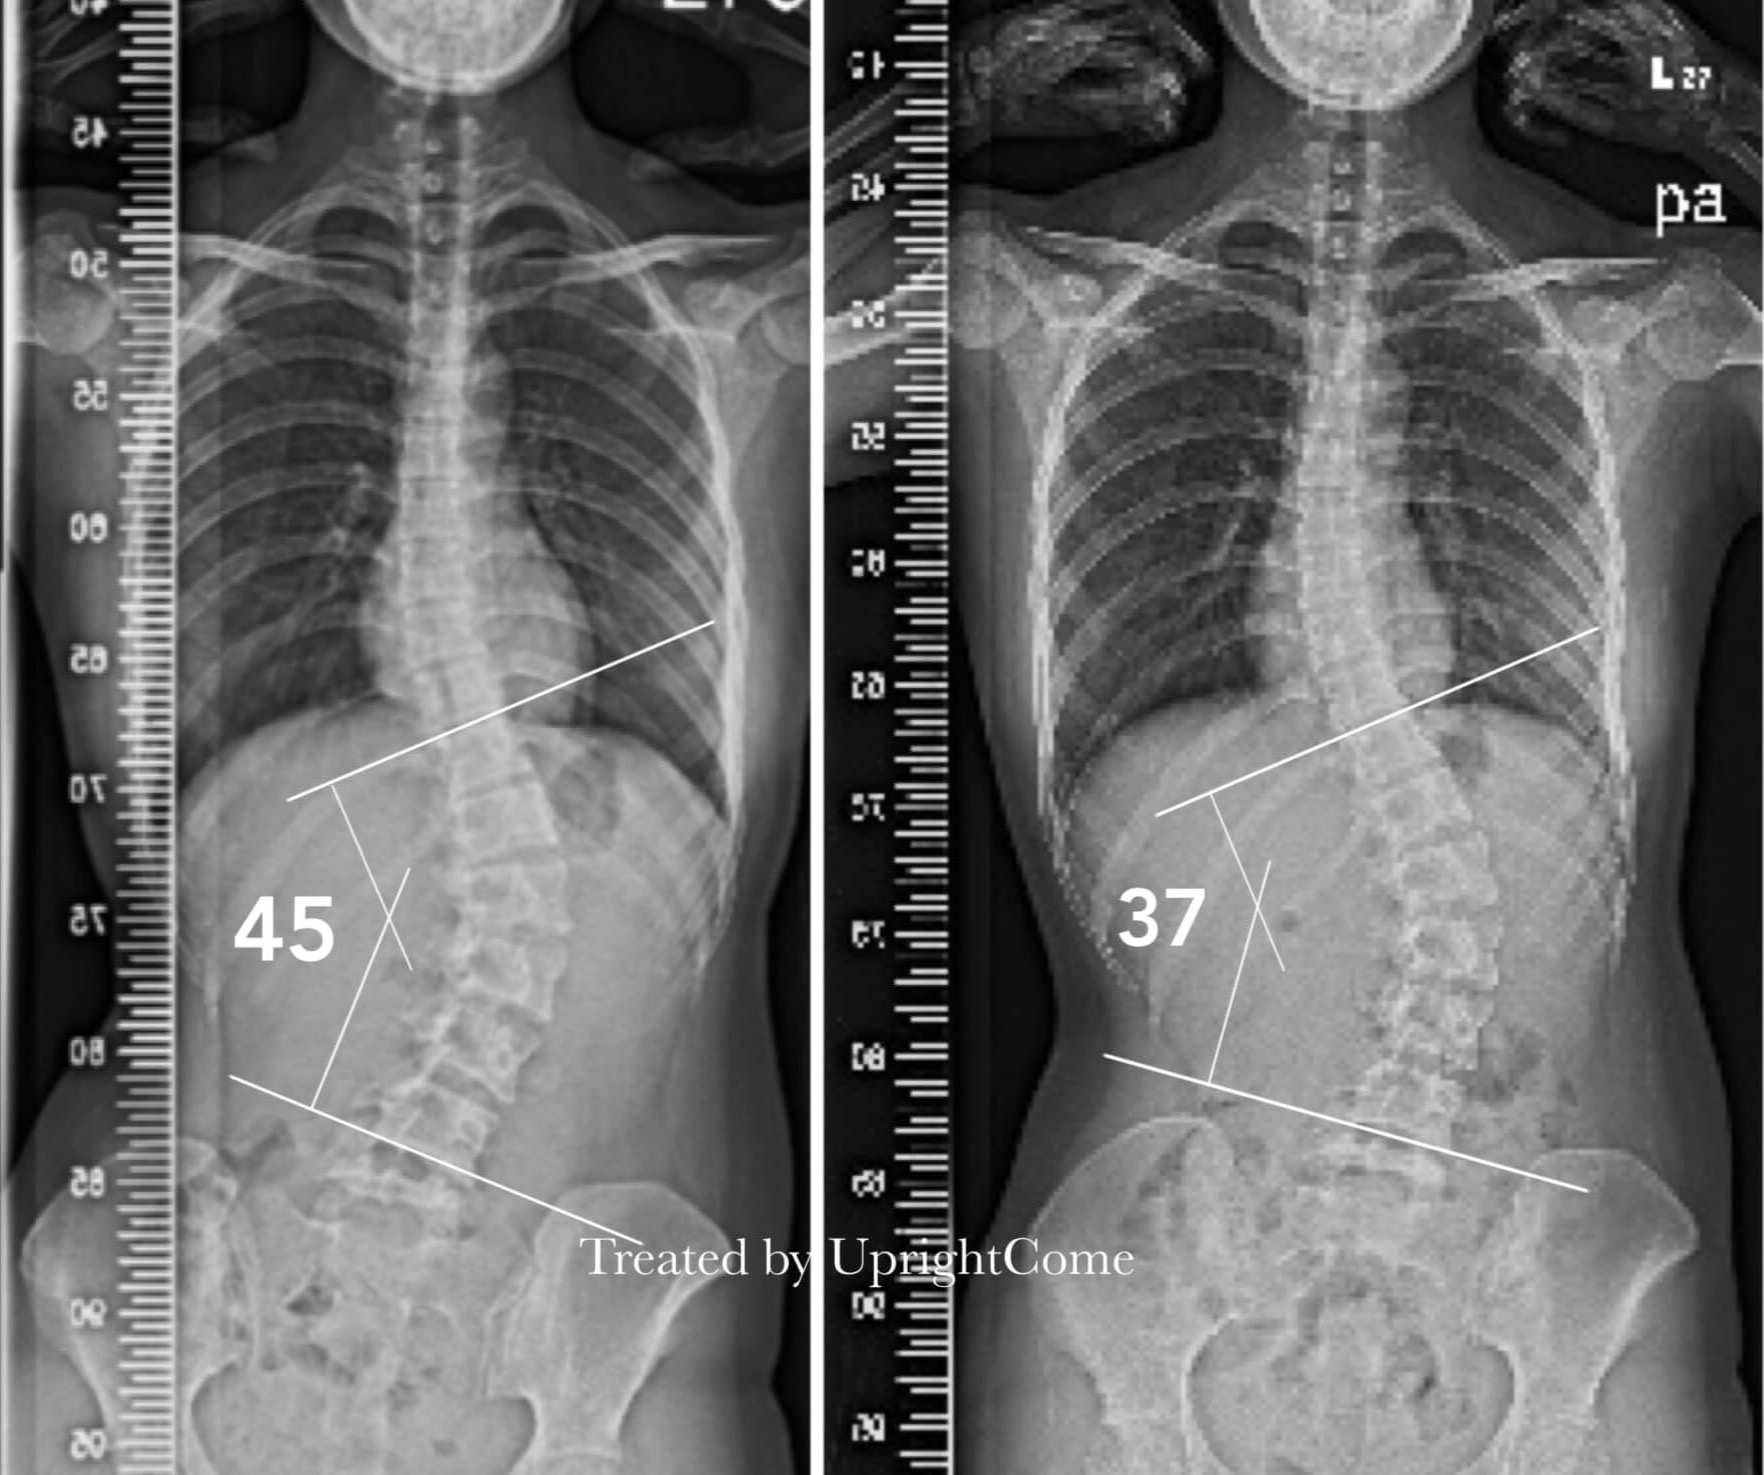

案例 23,21 歲,45 度側彎

![脊椎側彎患者經過側彎矯正治療後,腰椎側彎角度由45度減少到37度。]()